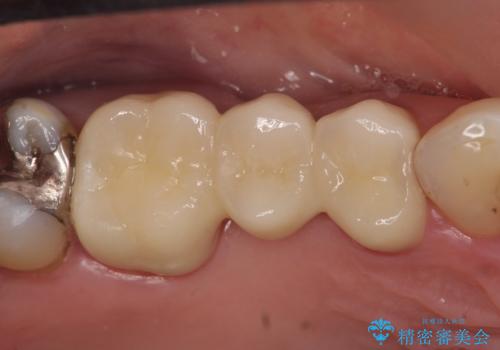

オールセラミッククラウン 歯根破折→抜歯→ブリッジ

- 右上の奥歯でものを咬むと痛むので診て欲しいといらっしゃった方の症例です。

診査の結果、歯根が破折しており保存不可能だったため抜歯し、ブリッジによる補綴を行いました。

今回用いたオールセラミッククラウンはジルコニアフレームという白い素材の上にセラミックを盛っているため、審美性が非常に高いのが特徴です。

また、ジルコニアは人工ダイヤモンドの材料にも使われているほど高い強度を持っており、そのためオールセラミッククラウンは審美性だけでなく、奥歯やブリッジの補綴も可能とするクラウンです。